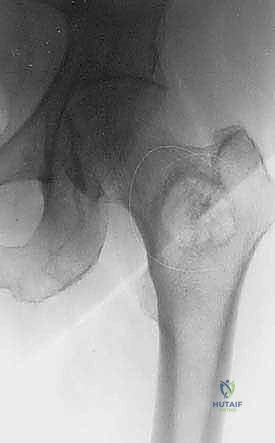

* عظم الفخذ (Femur): أطول وأقوى عظام الجسم، وإصابته تهدد قدرة المريض على المشي.

2. الكسور المرضية (Pathological Fractures)

الخوف الدائم من التعرض لكسر نتيجة حركة بسيطة يضع المريض في حالة من العزلة. يحدث الكسر المرضي نتيجة ضعف العظم لدرجة أنه ينكسر أثناء أداء نشاط يومي عادي مثل السعال، أو النهوض من الكرسي، أو الالتفاف في السرير.

1. حدوث كسر مرضي فعلي في عظم رئيسي (مثل الفخذ).

2. وجود خطر داهم بحدوث كسر (يتم حسابه عبر معايير طبية دقيقة تُعرف بـ Mirels' Score).

- الحالة الأولى: سيدة تبلغ من العمر 55 عاماً، متعافية من سرطان الثدي، عانت من ألم مبرح في الفخذ الأيمن وعجز كامل عن المشي بسبب كسر مرضي وشيك. بعد إجراء الفحوصات، قام الدكتور هطيف بإجراء جراحة تثبيت وقائي باستخدام مسمار نخاعي. في غضون 48 ساعة، استطاعت السيدة المشي بدون ألم، وعادت لممارسة حياتها وسط عائلتها.